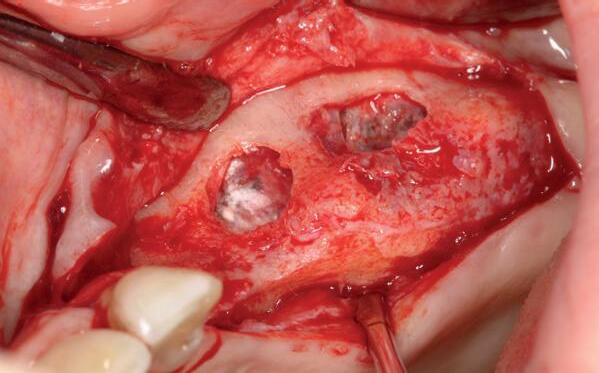

In deze casus is extractie van de 37 geïndiceerd in verband met een fistel en restpockets, zoals zichtbaar op de röntgenfoto’s (afbeelding 1). Duidelijk te zien is de forse peri-apicale ontsteking en het botverlies bij de 37, dat zowel richting buccaal als linguaal doorloopt. De 37 wordt atraumatisch verwijderd. Er is aan de linguale zijde veel bot verloren en er is sprake van een perforatie aan de buccale zijde.

Er wordt besloten om botmateriaal te plaatsen in de extractie-alveole. Vervolgens wordt het afgesloten met een titanium versterkt d-PTFE membraan (afbeelding 2). Na vier weken wordt het membraan verwijderd.

Zes maanden na extractie wordt het implantaat 37 geplaatst. Er is sprake van een goede genezing en de processushoogte en -breedte zijn behouden en opgebouwd. Ook is er zichtbaar gekeratiniseerd weefsel

gewonnen. De wond kan na het plaatsen van een healing abutment primair gesloten worden (Afbeelding 3a-3d).